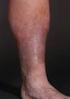

1 Medical Coverage Policy Varicose Vein Treatment sad EFFECTIVE DATE: POLICY LAST UPDATED: OVERVIEW Varicose veins are large superficial veins that have become swollen. These veins can be found anywhere in the body but are most common in the lower extremities. This policy describes various methods of treatment. PRIOR AUTHORIZATION Prior authorization is required for Blue CHiP for Medicare and recommended for Commercial products. POLICY STATEMENT All BCBSRI Products Treatment of symptomatic varicose veins is considered medically necessary when the medical criteria listed below are met for both treatment and the method. Mechanochemical ablation of any vein is considered not medically necessary as there is insufficient peer reviewed scientific literature that demonstrates that the procedure/service is effective. Embolization of the ovarian vein and internal iliac veins for the treatment of pelvic congestion is considered not medically necessary as there is insufficient peer reviewed scientific literature that demonstrates that the procedure/service is effective. BlueCHiP for Medicare Sclerotherapy when used in the treatment of telangiectasias is considered a cosmetic procedure and is not performed to correct a functional impairment. Medicare does not cover cosmetic procedures. Commercial Products Sclerotherapy when used in the treatment of telangiectasias is a contract exclusion as it is always considered to be a cosmetic procedure. MEDICAL CRITERIA BlueCHiP for Medicare and Commercial Medical treatment of varicose veins of the lower extremities is considered medically necessary when the medical criteria below are met: The patient must meet one of the listed criteria below: Varicosities causing pain or functional impairment, such as complications of venous stasis as in duration dermatitis or superficial ulceration not satisfactorily relieved by a trial of conservative medical management (e.g., rest with elevation, analgesics, compression hose) of one month duration, and there is reflux incompetency of greater saphenous vein and/or lesser saphenous and/or accessory saphenous vein (with the exception of all forms of sclerotherapy which requires a competent greater saphenous and/or lesser saphenous and/or accessory saphenous vein) Superficial thrombophlebitis of greater saphenous vein and/or lesser saphenous and/or accessory saphenous vein Hemorrhaging from a ruptured varix 500 EXCHANGE STREET, PROVIDENCE, RI MEDICAL COVERAGE POLICY 1

2 In addition to meeting the above treatment criteria, the patient must meet the following criteria for the methods of treatment specified below: Ligation and Stripping If the greater saphenous and/or lesser saphenous and/or accessory saphenous vein is incompetent Endovenous radiofrequency or laser ablation If the greater saphenous vein and/or lesser saphenous and/or accessory saphenous vein is incompetent. See Surgical ligation procedure below including SEPS, for treatment of perforator veins. Sclerotherapy The veins must be >2 mm and <6 mm since veins greater than 6 mm in diameter are more successfully treated with surgery; and If the greater saphenous and/or lesser saphenous and/or accessory saphenous vein is competent; or If the greater saphenous and/or lesser saphenous and/or accessory saphenous vein has been removed or ablated. Sclerotherapy services for 3 sessions over a 12 month period will be required/recommended for preauthroization. Requests for additional sclerotherapy services will be reviewed to support the need for additional treatment. Echosclerotherapy Limited to the perforator veins greater than 3.5 mm in size; and If the greater saphenous and/or lesser saphenous and/or accessory saphenous vein is competent; or If the greater saphenous and/or lesser saphenous and/or accessory saphenous has been removed or ablated. Transilluminated powered phlebectomy and ambulatory phlebectomy If the greater saphenous and/or lesser saphenous and/or accessory saphenous vein is competent; or If the greater saphenous and/or lesser saphenous and/or accessory saphenous vein has been removed or ablated. Surgical ligation (including subfascial endoscopic perforator surgery [SEPS]), or endovenous radiofrequency, or laser ablation of incompetent perforator veins There is demonstrated perforator reflux; and Must be associated with chronic venous insufficiency when the following conditions have been met: and previously eliminated; The superficial saphenous veins (greater, lesser, or accessory saphenous and symptomatic varicose tributaries), have been eliminated Leg ulcers have not resolved following combined superficial vein treatment and compression therapy for at least 3 months; and The venous insufficiency is not secondary to deep venous thromboembolism. Note: Cluster veins may be treated at the time of any of the primary procedures without a separate review. BACKGROUND Varicosities are often caused by incompetence of the valvular system within the vein, from intrinsic weakness of the vein wall, from high intraluminal pressure, and rarely, from arteriovenous fistulas. In severe cases, these varicose veins may cause severe pain and swelling of an extremity, as well as stasis changes such as dermatitis and ulceration. 500 EXCHANGE STREET, PROVIDENCE, RI MEDICAL COVERAGE POLICY 2

3 Primary varicose veins originate in the superficial system (comprised of the greater and lesser saphenous veins) and occur two to three times more frequently in women than in men. Secondary varicose veins result from deep venous insufficiency and incompetent subfacial perforator veins or deep venous occlusion causing enlargement of superficial veins serving as collaterals. Chronic venous insufficiency can be connected to varicose veins or it could not. Chronic venous insufficiency is related to incompetence of 1 or more branches of the peripheral venous system, i.e., of the deep or superficial system, or the perforators that connect the two. Untreated venous insufficiency in the deep or superficial system causes a progressive set of symptoms involving pain, swelling, skin changes, and eventual tissue breakdown. Controversy remains among vascular surgeons regarding the role of perforator incompetence in the medical and surgical treatment of chronic venous insufficiency. In general, there is an incomplete understanding of how the hemodynamics of one venous system (i.e., superficial, perforator, deep) may affect the hemodynamics of the other. Because of this and other factors, there is inadequate evidence to permit scientific conclusions about the efficacy of subfascial endoscopic perforator surgery ( SEPS). Telangiectasis (spider veins, spider bursts, web veins, thread veins, dilated venules) are permanently dilated blood vessels that create fine, red lesions or lines with radiating limbs on the skin. They are usually limited to the dermis and are often the result of hormonal effects on the soft skin appearing during the menarche, pregnancy, menopause or at other times of hormonal disturbance. They rarely have any physical symptoms but may present a cosmetic concern. Pelvic congestion syndrome is a condition of chronic pelvic pain of variable location and intensity, which is associated with dyspareunia and postcoital pain and aggravated by standing. The syndrome occurs during the reproductive years, and pain is often greater before or during menses. The underlying etiology is thought to be related to varices of the ovarian veins, leading to pelvic congestion. As there are many etiologies of chronic pelvic pain, the pelvic congestion syndrome is often a diagnosis of exclusion, with the identification of varices using a variety of imaging methods, such as magnetic resonance imaging (MRI), computed tomography (CT) scanning, or contrast venography. For those who fail medical therapy with analgesics, surgical ligation of the ovarian vein has been considered. More recently, embolization therapy of the ovarian and internal iliac veins has been proposed. Vein embolization can be performed using a variety of materials including coils, glue, and gel foam. The available literature regarding emoblization therapy for the treatment of pelvic congestion syndrome is inadequate to draw clinical conclusions; thus this treatment is considered not medically necessary. Types of Treatment Vein ligation and stripping: Veins are tied shut (ligation) and removed (stripping) through small incisions. The procedure is typically used in severe cases in which varicose veins cause pain or skin ulcers. It is normally performed under general anesthesia. Radiofrequency Ablation (RFA): Also known as VNUS Closure, is intended for the endovascular coagulation of blood vessels in patients with superficial vein reflux. This procedure uses endovenous electrodes to deliver radiofrequency energy that heats the vessel wall, causing it to shrink and occlude. It is offered as an alternative to vein ligation or stripping to treat saphenous venous reflux. Laser Ablation: Also known as endovenous laser therapy (EVLT ) uses an energy source (either laser or radiowave) which is designed to damage the intimal wall of the vessel, resulting in fibrosis and ultimately obliteration of a long segment of the vein. One commonly used system is the Diomed 810-nm laser. Endovenous Mechanochemical Ablation: Endovenous mechanochemical ablation utilizes both sclerotherapy and mechanical damage to the lumen. Following ultrasound imaging, a disposable catheter with a motor drive is inserted into the distal end of the target vein and advanced to the saphenofemoral junction. As the catheter 500 EXCHANGE STREET, PROVIDENCE, RI MEDICAL COVERAGE POLICY 3